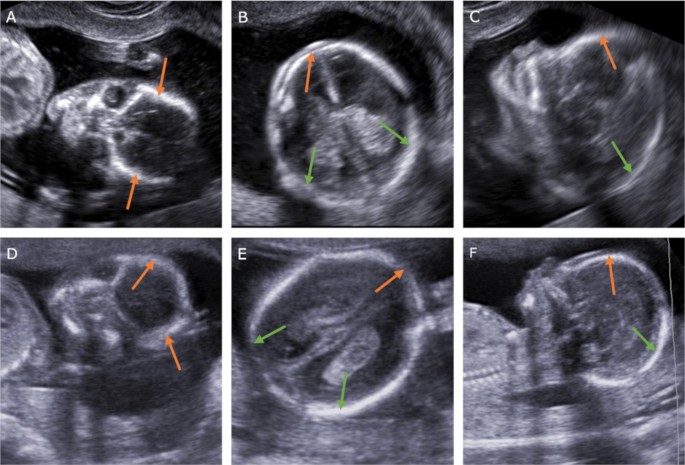

The Role Of The Beret Sign And Other Markers In Ultrasound Diagnostic Of The Acrania Exencephaly Anencephaly Sequence Stages Springerlink

Cns Abnormalities At 11 14 Weeks